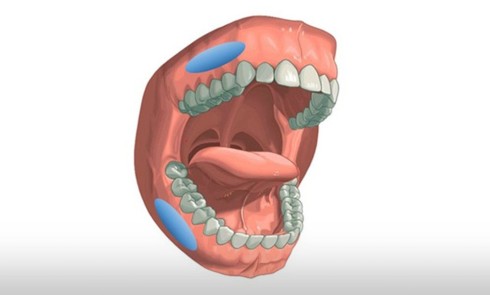

Le Syndrome d’apnées et hypopnées obstructives du sommeil (Sahos) est une pathologie chronique, fréquente dans la population générale d’âge moyen,...Le Sahos et le chirurgien-dentiste : dépistage au quotidien

Le Syndrome d’apnées hypopnées obstructives du sommeil (Sahos) est caractérisé par des épisodes récurrents d’obstruction complète (apnée) ou partielle (hypopnée)...Syndrome d’apnées-hypopnées obstructives du sommeil : spécificités chez l’enfant

Spécificités cliniques du Sahos de l’enfant Comme chez l’adulte, le Syndrome d’apnées-hypopnées obstructives du sommeil (Sahos) de l’enfant correspond à...Le Sahos : traitement par Orthèse d’avancée mandibulaire (OAM)

Place des OAM dans le traitement du Sahos [1 2 3] Définition des OAM Une orthèse est un dispositif médical amovible qui...Maladie de Parkinson et prise en charge bucco-dentaire